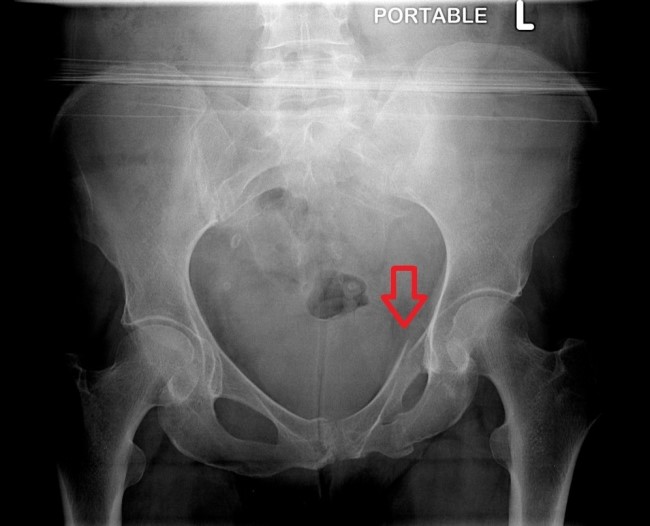

![]()

입원했을때 찍은 영상인데 뒷다리를 못쓰고 앞다리로 기어다녔습니다. ㅠ어쩔까요..?

따라서 수술 계획은 다음과 같습니다! (1) 천장관절 탈구 오른쪽 골반의 탈구 – 원래는 골반에 가해지는 부하를 줄이기 위해 긴 나사로 탈구를 고정한 후 오른쪽 고관절 절제술을 시행해야 했지만 – 보호자분의 스플릿 상담 후 , 고관절 절제술 만하고 예후를 관찰하기로 결정했습니다. – 골반의 무게를 줄이면 자연스럽게 치유될 가능성이 있기 때문입니다. (1-2) 오른쪽 골반뼈 비구의 골절. , 비구 골절은 별도의 수술이 필요하지 않다고 판단한다. (2) 왼쪽 골반뼈의 장골날개 골절 – X-ray상 2조각의 골절 소견.